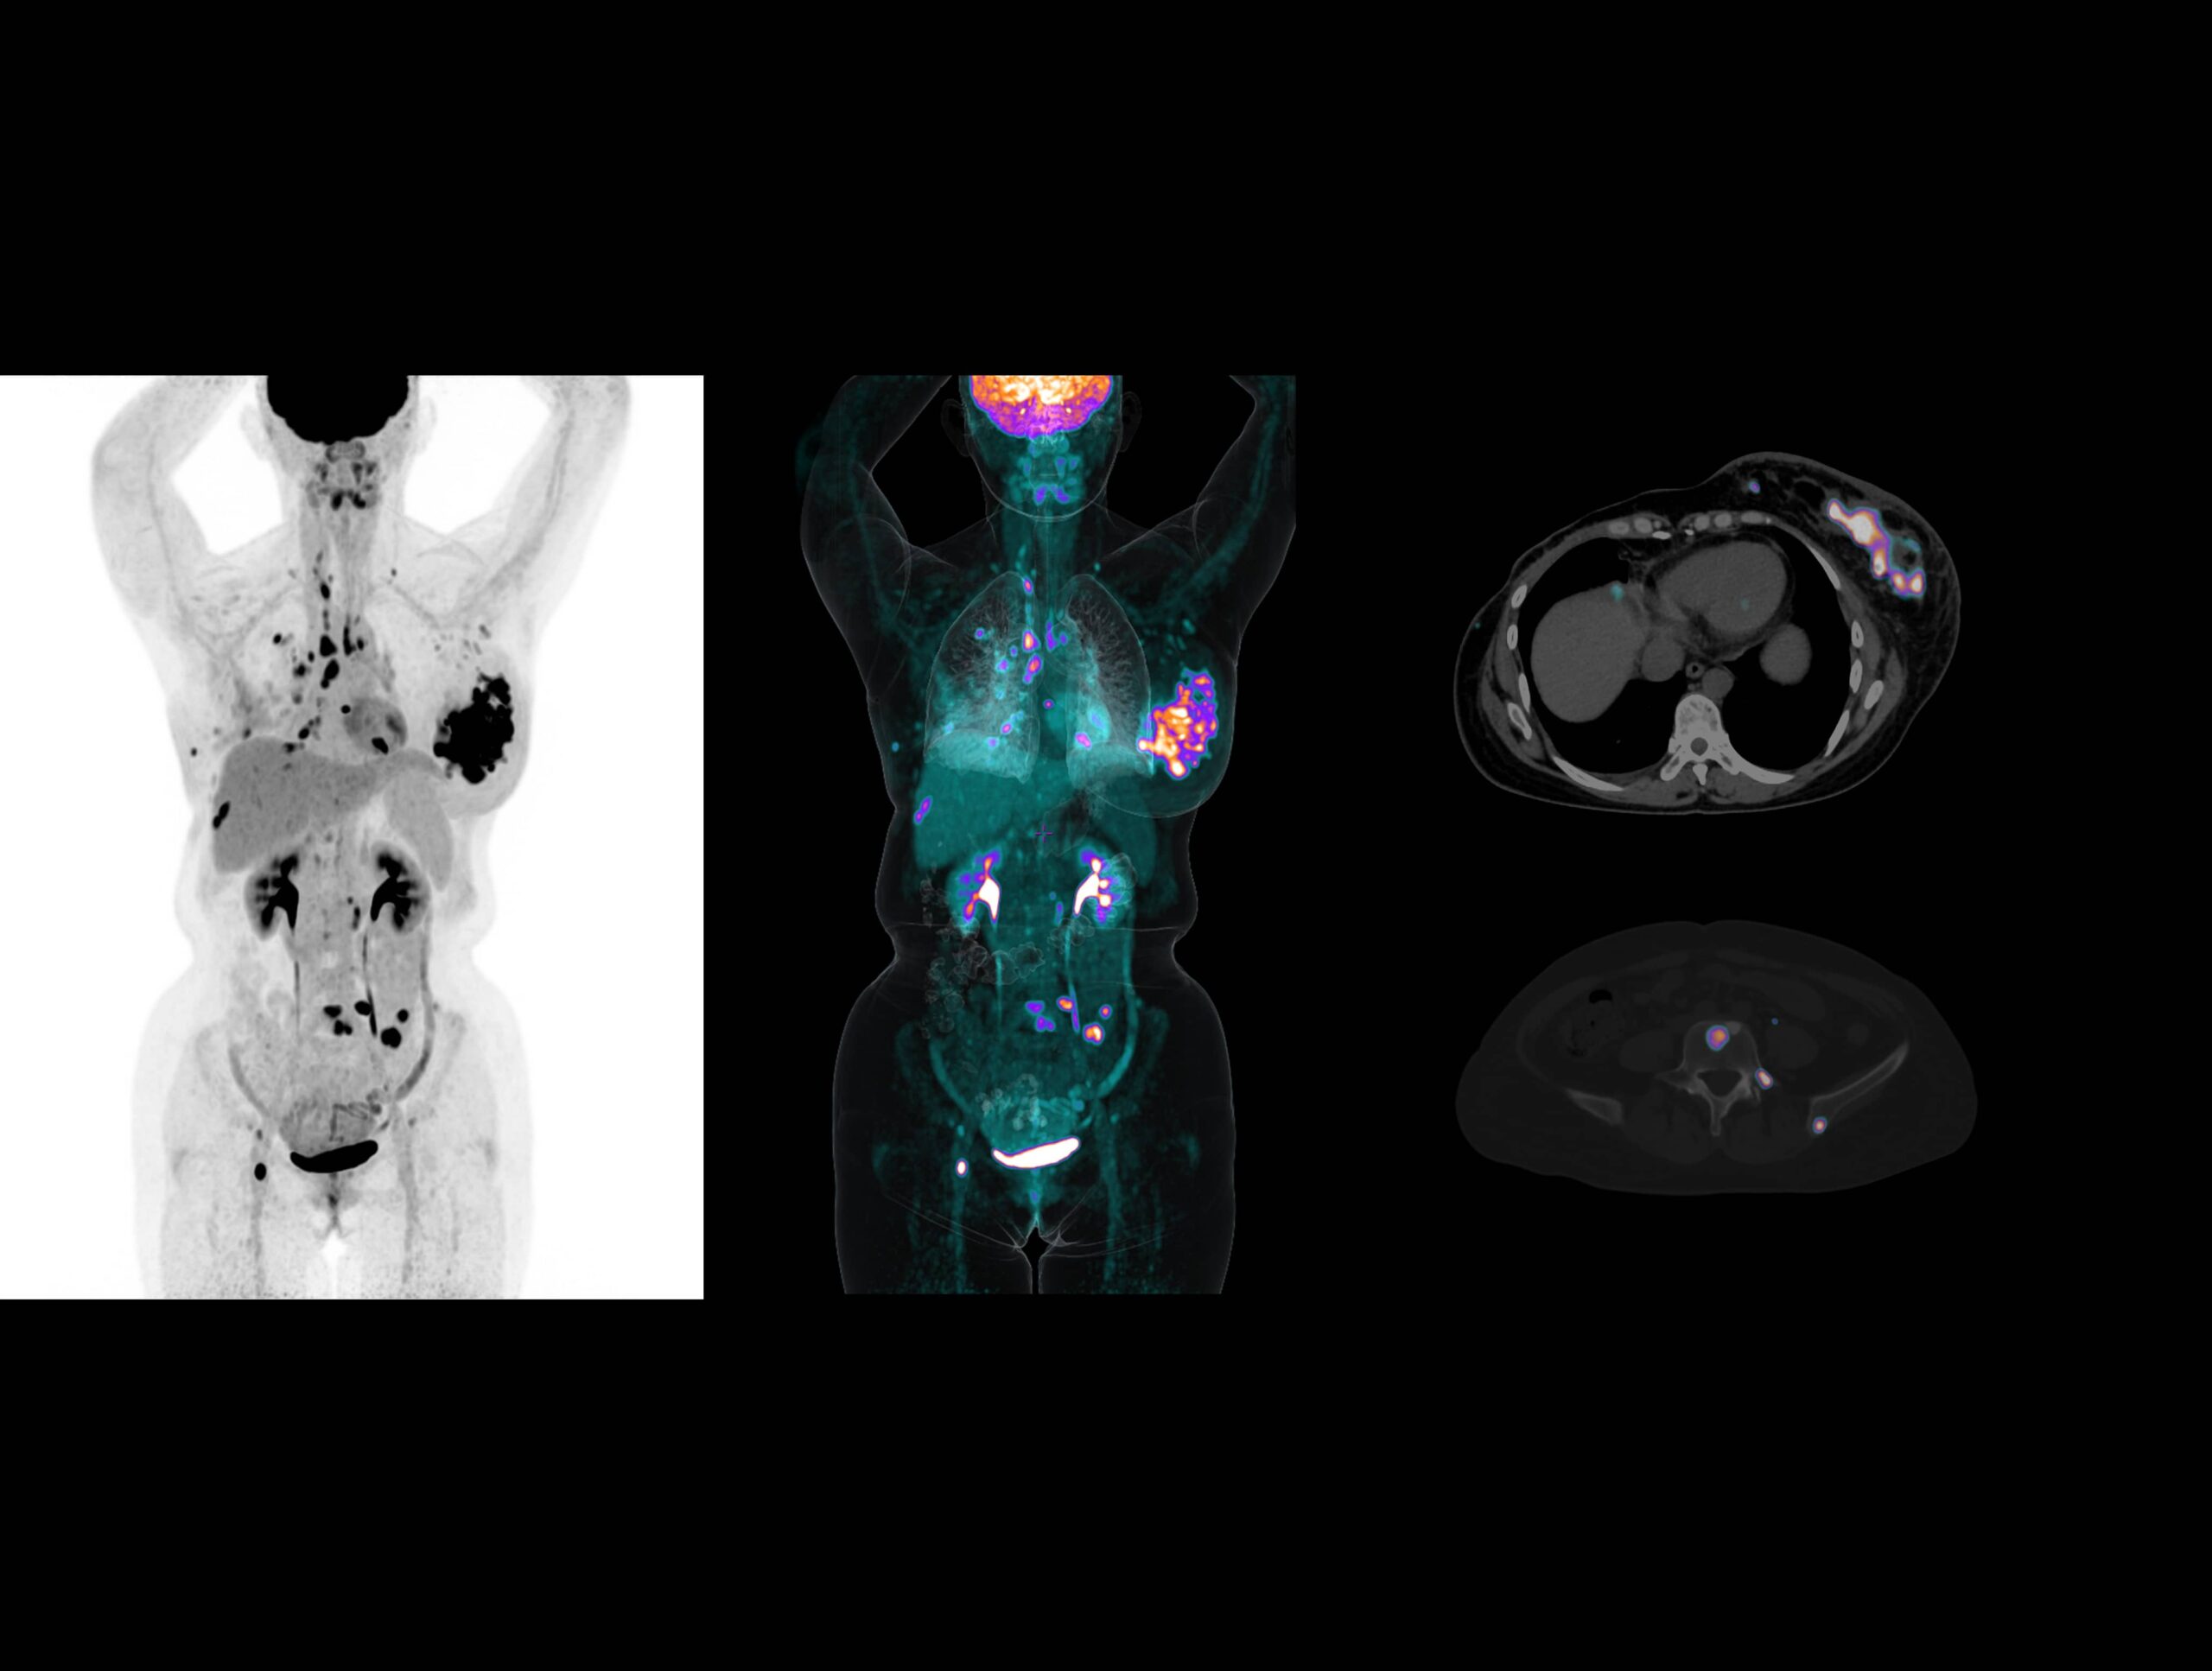

Metastazele extinse ale cancerului de sân sunt dezvăluite clar de sistemul high-resolution cu TOF ultra-rapid

Imagistică de înaltă rezoluție obținută cu radiotrasor marcat cu galiu la doză redusă